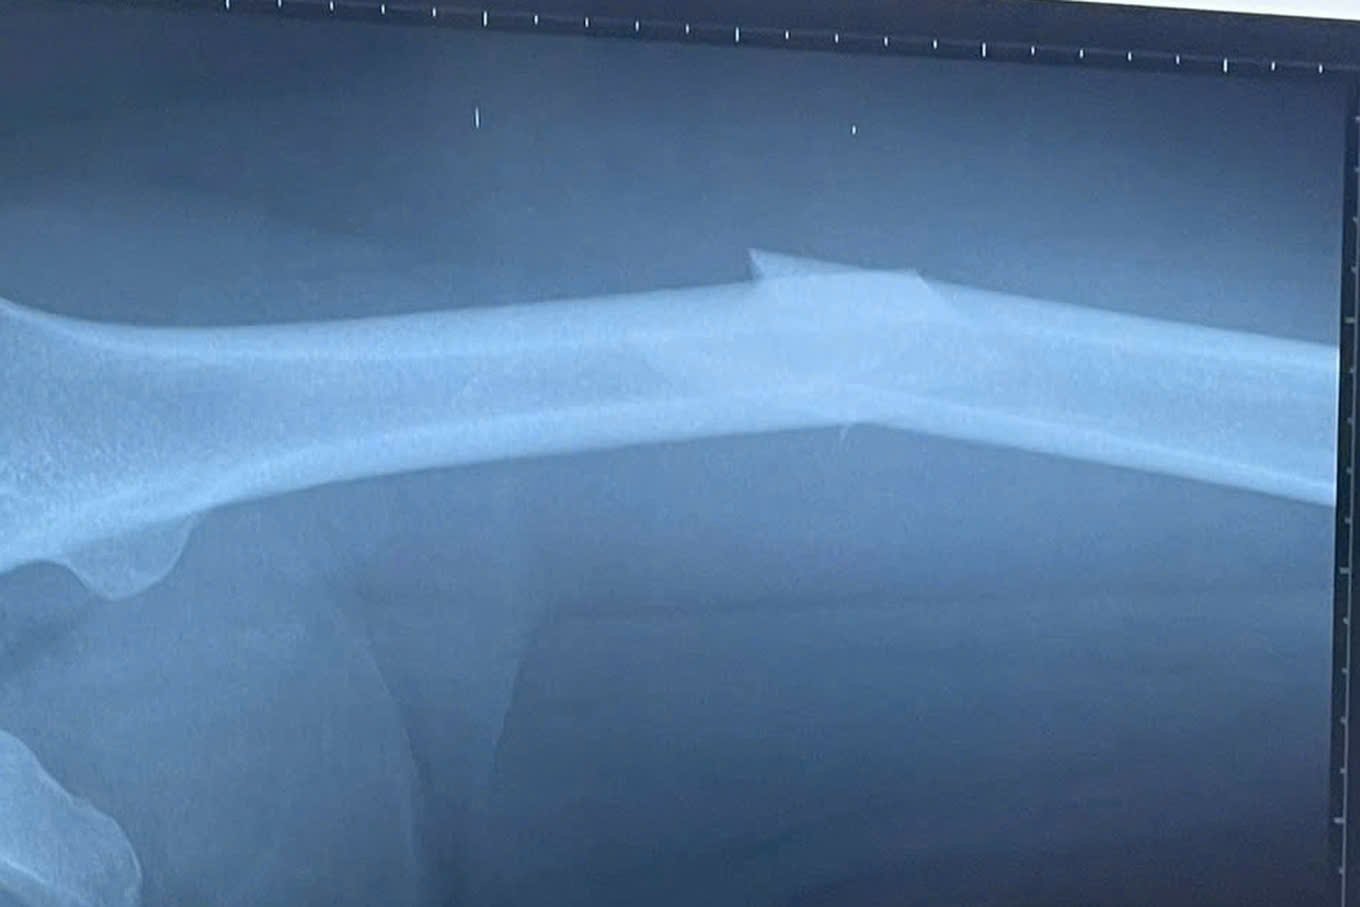

در آوریل ۲۰۲۵، کی هان، مدل و همسر بازیکن فوتبال، مک هونگ کوان، هنگام بازی پیکلبال در شهر هوشی مین، پایش شکست. پیش از آن، در ورزشگاه کائو گیای ( هانوی )، مردی ۵۵ ساله تنها پس از ۲۰ دقیقه بازی سکته مغزی کرد. این دو حادثه باعث ایجاد جنجال در جامعه پیکلبال شد و بسیاری از باشگاهها را مجبور کرد تا رویههای گرم کردن خود را سختتر کنند.

دکتر نگوین شوان آن، متخصص ترومای ارتوپدی، گفت که بیمارستان هر روز موارد بیشتری از آسیبهای ناشی از پیکلبال، از پیچخوردگیهای خفیف گرفته تا پارگی رباطها و تاندونهای آشیل، دریافت میکند. دکتر شوان آن گفت: «نکات مشترک، میل به توپ، حرکات عجولانه و عدم تکنیک است. پیکلبال برخلاف تصور بسیاری از مردم، ورزشی آرام نیست و به واکنشهای سریع و قدرت پرش نیاز دارد، بنابراین اگر به درستی گرم نکنید، خطر بسیار زیاد است.»

دکتر وو هوآ خان، رئیس بخش مدیریت کیفیت بیمارستان ارتوپدی شهر هوشی مین، نیز اذعان کرد: «بسیاری از مردم زمینهای سفت و سخت را انتخاب میکنند، برای نجات توپ شیرجه میزنند و خطر آسیبدیدگی را افزایش میدهند. به خصوص برای افرادی که بیماری قلبی عروقی زمینهای دارند، حرکات ناگهانی میتواند به راحتی منجر به حوادث خطرناک شود.»